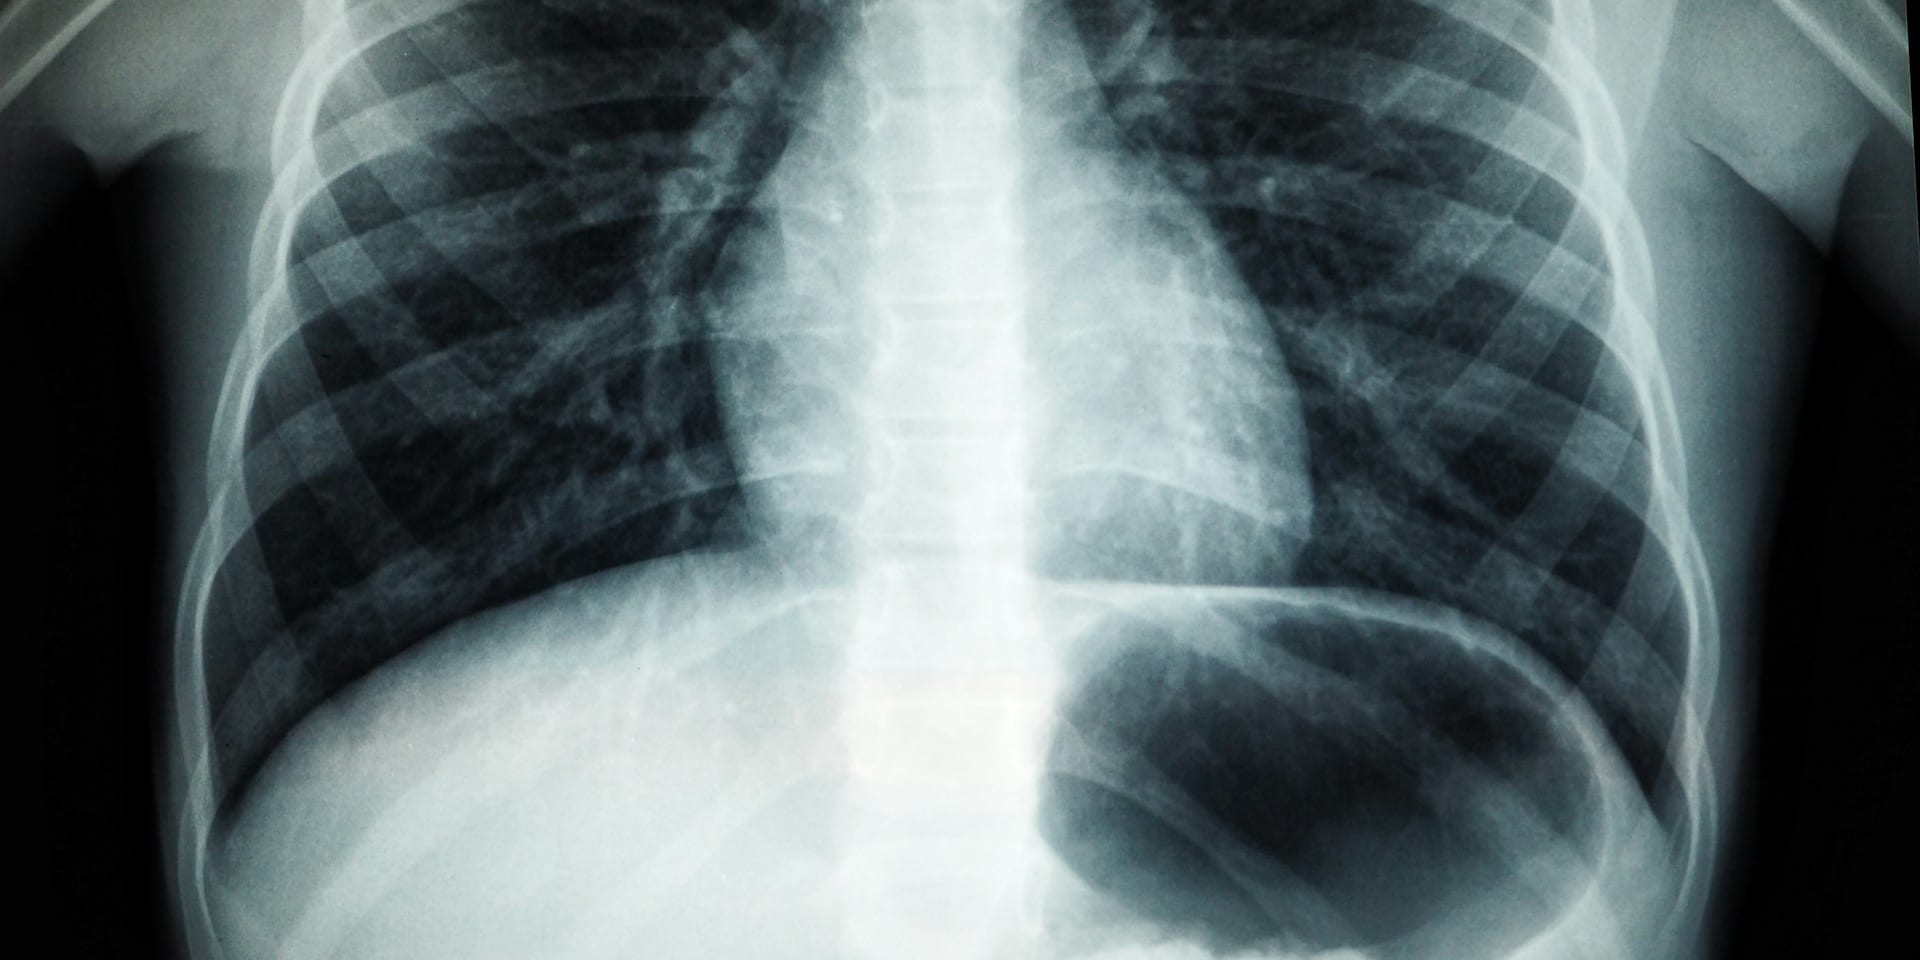

Tuberculose is een infectieziekte veroorzaakt door de bacterie Mycobacterium tuberculosis. Deze bacteriën kunnen verschillende organen infecteren, maar staan er vooral om bekend de longen aan te tasten. Tuberculose verspreidt zich via de lucht, door middel van microdruppeltjes die in de lucht terechtkomen wanneer een besmette persoon hoest, niest of praat.